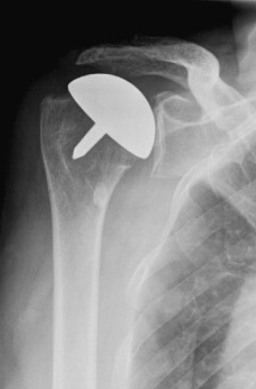

A partial shoulder replacement involving the replacement of only the ball or the humeral head with a metal ball and stem. This surgery may be recommended when the humeral head is severely damaged but the socket or the glenoid fossa is normal.

A partial shoulder replacement involving the replacement of only the surface of the ball or the humeral head with an artificial cap without the stem. This is an alternative to the stemmed hemiarthroplasty allowing for more bone preservation.